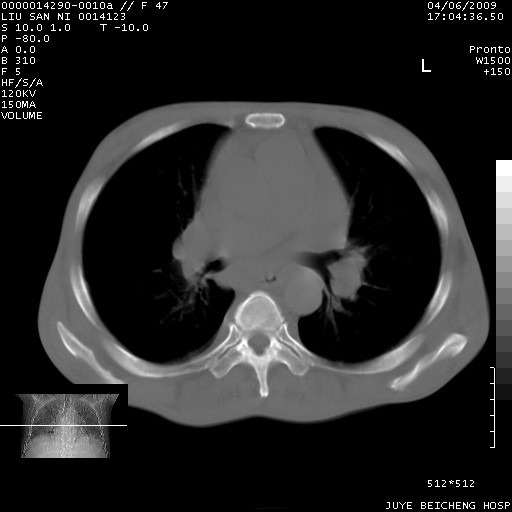

以下是引用前行在2009-4-7 10:31:00的发言:[br]肝脾肿大;双肾增大,双肾盂少量积水可能,肾膜膜增厚,肾周间隙增宽,并见桥间隔,提示结缔组系统疾病、系统性红瘢狼疮肾可能性大。继发右侧胸腔、心包、腹腔积液。